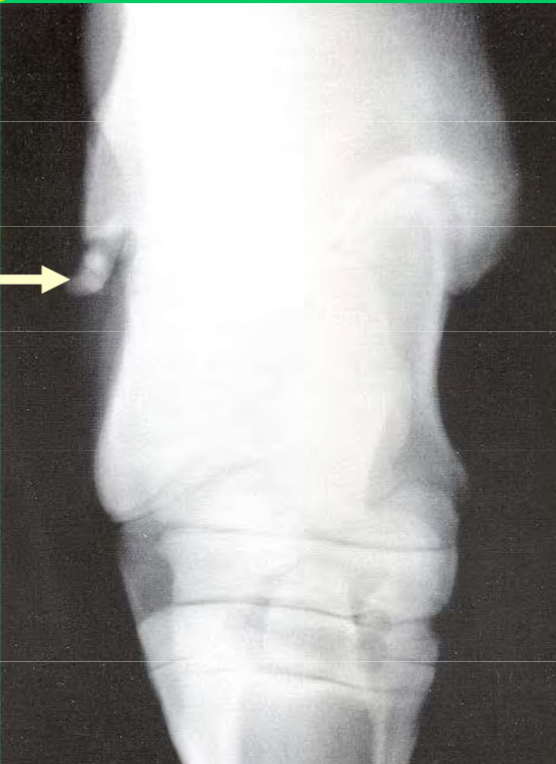

What is this lesion

OCD of the lateral trochlear ridge